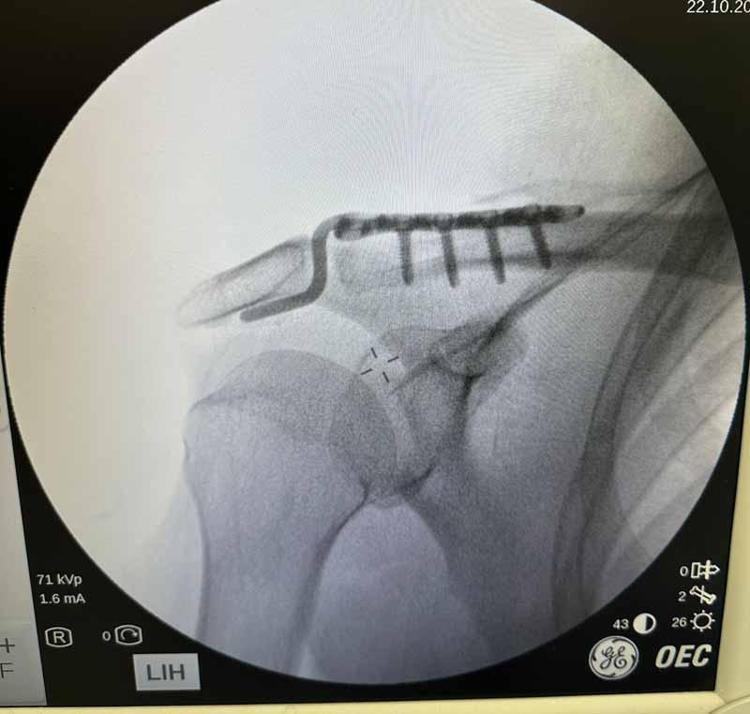

Kentteki bir kortta düştükten sonra omzunda çıkık oluşan Rençber’e, başvurduğu bazı merkezlerde yaş nedeniyle ameliyat önerilmedi. Batman Eğitim ve Araştırma Hastanesi Ortopedi ve Travmatoloji Uzmanı Dr. Mehmet Yavuz Başer’in değerlendirmesi sonrası hasta ameliyata alındı. Rençber’in omzuna kemik yapısına uyumlu, nadir kullanılan özel bir plak takıldı. Ameliyatın ardından fizyoterapi süreci başlatılan hasta, ağrılarının azalmasıyla günlük hareketlerini yapabilir hale geldi ve taburcu edildi.

Muayenesini yaptık. Sosyal olarak aktif birisi olduğu için ameliyat kararını daha uygun gördük. Ameliyatı çok şükür güzel geçti, başarılı geçti. Nadir kullanılan bir plaktan kullandık. O da hastamıza tam olarak uydu.